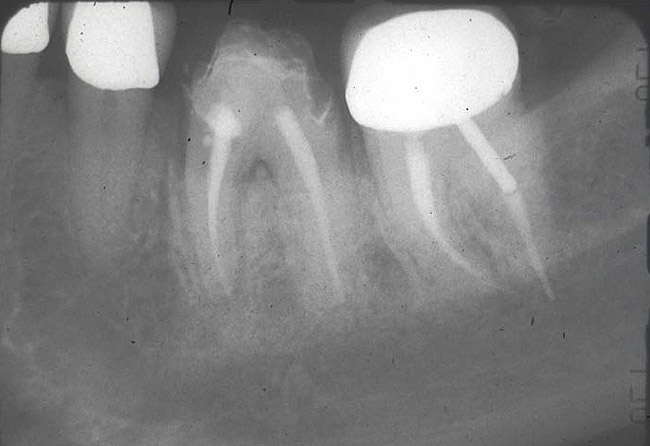

Figure 2  The mandibular first molar is hopeless due to presence of a vertical fracture. At the time treatment was performed, techniques were not available to ideally position an implant of desired dimension at the time of molar extraction.

Figure 2

Figure 3  Following tooth sectioning and extraction, defect debridement, and utilization of appropriate regenerative materials, extensive bone regeneration is noted in the area of the first molar. An implant of the desired dimension may now be placed in an ideal prosthetic position.

Figure 3

Figure 4  An implant with a 4.8-mm-wide body and a 6.5-mm-wide restorative platform has been restored with an abutment and crown; it has been in function for more than 10 years.

Figure 4

Implant placement at the time of mandibular molar extraction should never be attempted if there is any doubt about the ability to place an ideal dimension implant in the appropriate restorative position and attain primary stability. In such a situation it is better to first perform regenerative therapy at the time of tooth removal and place the implant in a subsequent surgical session (Figure 2 through Figure 4).